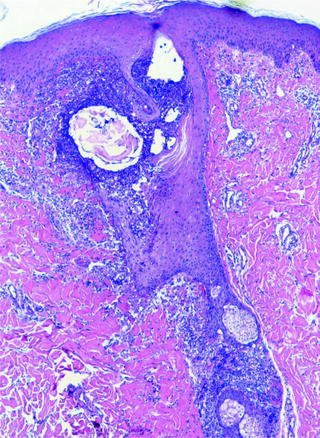

Pathology

On histology folliculitis presents with inflammatory cells in the wall and ostia of the hair follicle (see Fig. 4). The inflammation may be limited to the superficial aspect of the follicle, involving the infundibulum or it can affect both the superficial and deep aspect of the follicle. The types of inflammatory cells vary depending on the etiology of the folliculitis and/or the stage at which the biopsy specimen was obtained. For example, a neutrophilic infiltrate can be seen in more acute cases, whereas more chronic cases may have histocytic cells [11].

Fig. 4.

Histopathologic findings of a folliculitis. Suppurative process involving both the superficial and deep portion of the follicle